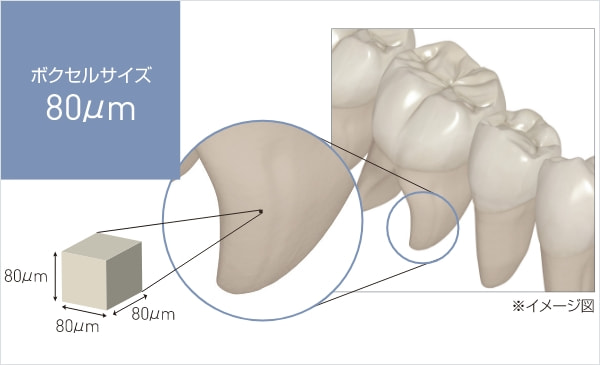

高精細なCT撮影を

最小ボクセルサイズ80μmでの高精細撮影 ※フリーモードで Φ40mm×H40mm 選択時

撮影範囲を予めプリセットした撮影モードに加え、撮影範囲を5mm単位で可変可能なフリーモードを搭載しています。

照射野を絞る事で、最小ボクセルサイズ80μmの高精細画像が取得できます。

ボクセルサイズとは?

ピクセルは、2D画像を構成する最小単位の正方形を意味するのに対して、ボクセルは3D画像における最小単位の立方体を意味します。

ボクセルサイズが小さいほど理論上、より高精細な画像になります。